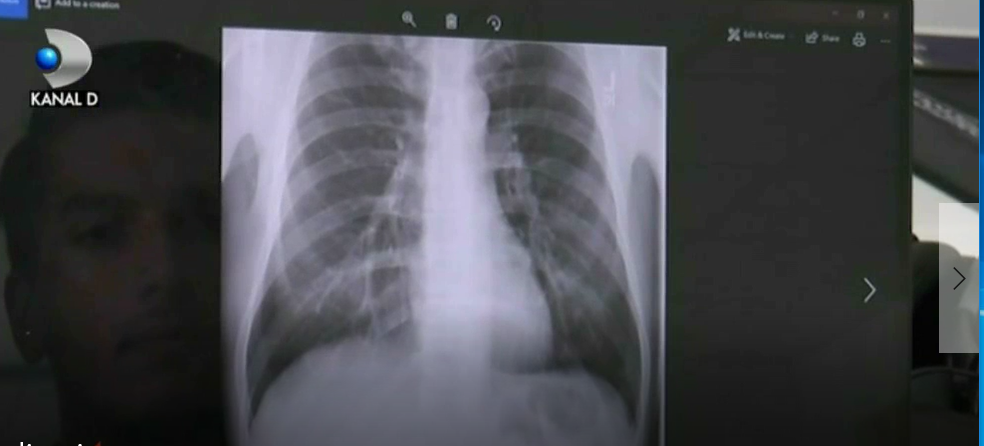

O aplicatie online citeste gratuit radiografii si pune diagnostice. Este inventia unor studenti de la Universitatea Politehnica din Timisoara

Tinerii au creat un program de inteligenta artificiala care vine in ajutorul medicilor. Detalii in VIDEO: